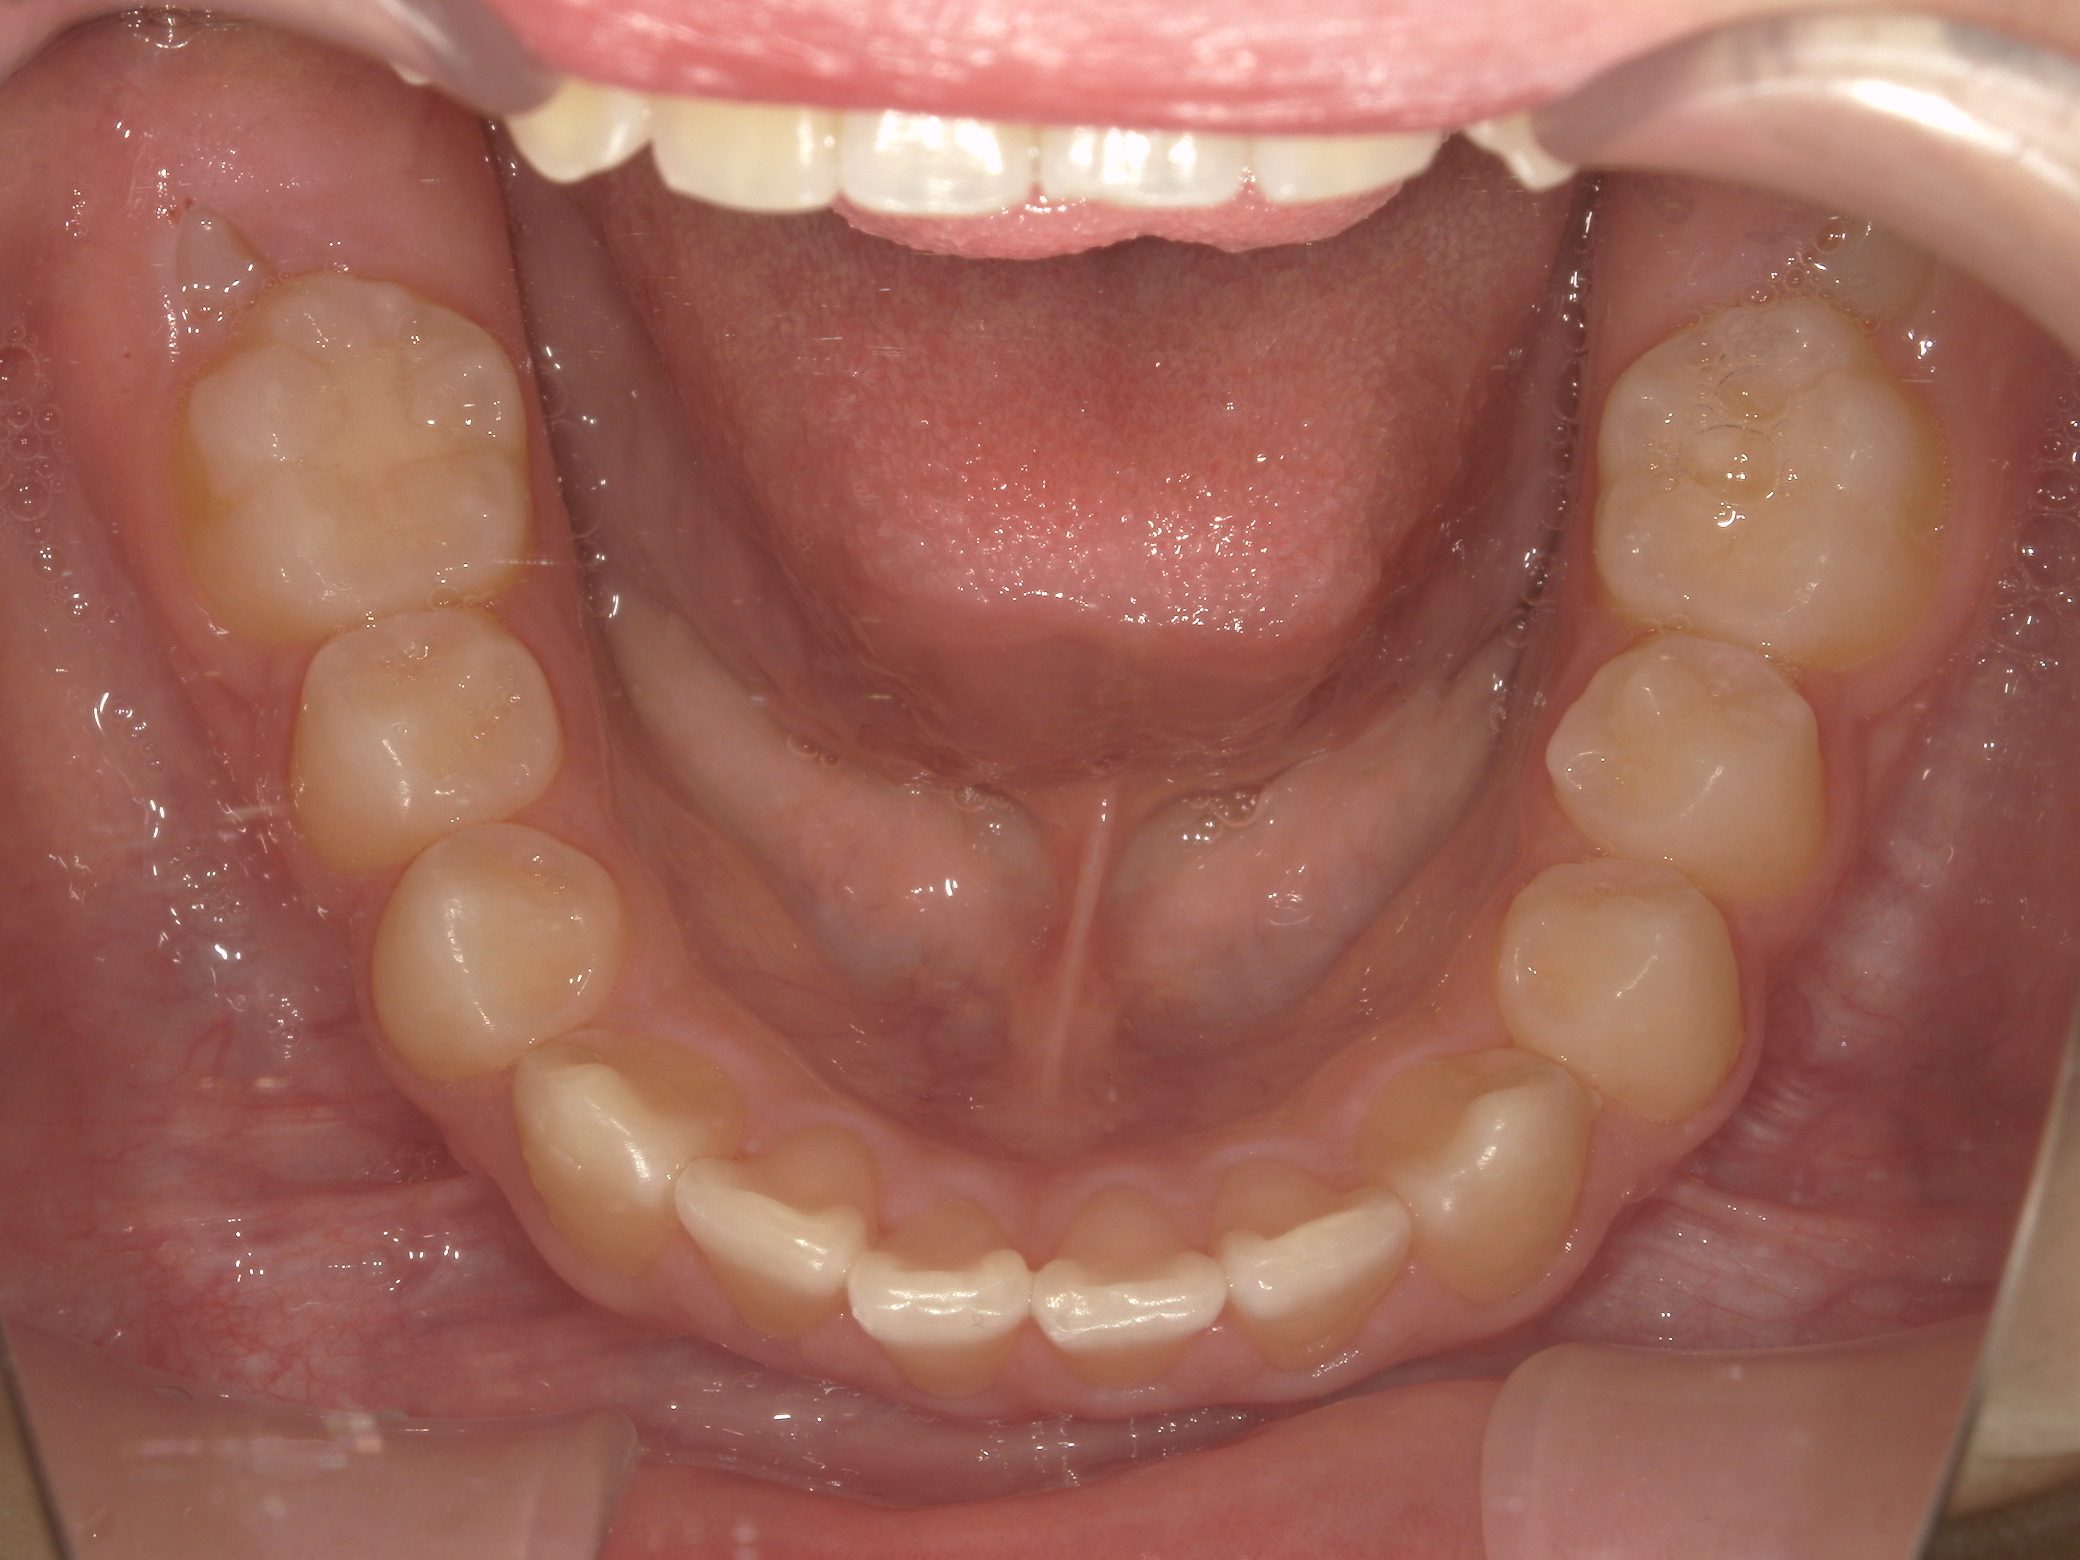

【小学生】 8歳 インビザライン矯正 過蓋咬合(深い咬み合わせ)と叢生(でこぼこ)を改善

小学生で開始

インビザライン ファースト

でこぼこ

非抜歯

1期治療のみで改善

Before

After

治療期間

1年4カ月年

治療開始

8歳

種類

インビザライン矯正

使用装置

インビザラインファースト(こどものインビザライン)

コメント

転勤族ということもあり、時間に制限がありましたが、患者さんがしっかり装置をつけてくれたので お引越しまでに終了することができました。

途中 側方の歯がどんどん生え変わって 最終的には全部永久歯で終了しました。

咬み合わせが深い場合、インビザラインファーストは咬み合わせを浅くするのに適しています。